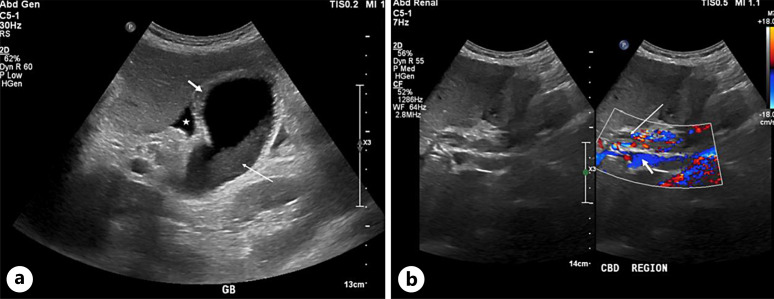

Case presentation: A 60-year-old male patient with multiple comorbidities presented with fever, chills, and cough for 1 day. In the emergency department, he tested positive for COVID-19 by PCR and his chest X-ray revealed features suggestive of pulmonary edema. The patient was intubated and admitted to the Medical Intensive Care Unit (MICU) for management of COVID-19 pneumonia with pulmonary edema. During hospitalization, he developed cardiac complications that required targeted management. Approximately 1 week after admission, his liver enzymes began to rise. Although drug-DILI was initially suspected and hepatotoxic medications were discontinued with the initiation of ursodeoxycholic acid (UDCA), the liver function tests (LFTs) remained elevated. Subsequent magnetic resonance cholangiopancreatography revealed periportal inflammation with intrahepatic biliary dilatation and stricturing, findings consistent with COVID-19 induced cholangiopathy. The UDCA dosage was doubled, resulting in gradual biochemical improvement; however, the patient ultimately discharged against medical advice.